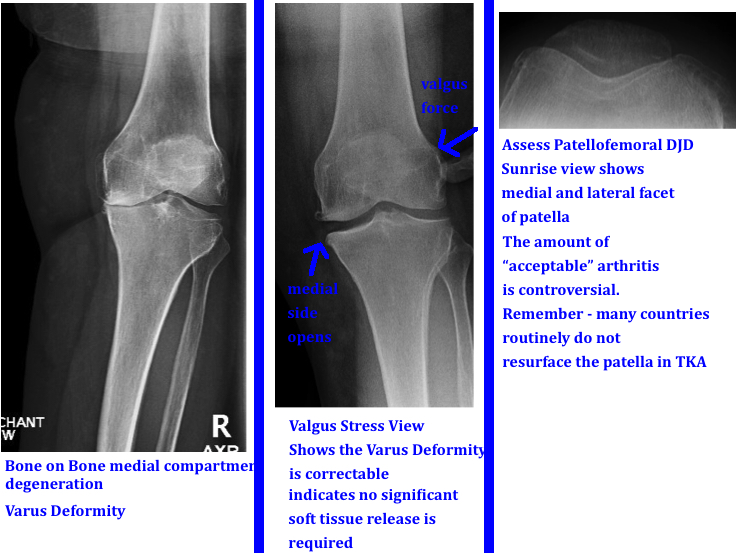

Knee Xray Eorif from eorif.com This view is used to assess the patellofemoral articulation, which may be altered by degenerative joint disease. What cpt codes would be appropriate for the following: During flexion/extension, the patella slides in the trochlea (notch) and is located in the middle of the trochlea. Code 73565 is used for a standing view of both knees when morphology (form and structure) is examined. This examination is performed typically on patients with osteoarthritis and for presurgical planning. If the patient is seated on the radiographic table, the patient must hold the ir securely in place behind the knee. To evaluate patellofemoral space, tilt, and alignment ; Knee flexion contractures can effect quality and accuracy of measurements lateral view:

The sunrise view is a tangential look at the flexed knee. Two views (internal and external) better demonstrating the knee joint in the absence of ct To evaluate patellofemoral space, tilt, and alignment ; It clearly displays the kneecap and is most useful for diagnosing arthritis between the kneecap and the thigh bone. View utilized to demonstrate intercondylar space, often used for oa and suspected tibial plateau fractures rosenberg's view.

During flexion/extension, the patella slides in the trochlea (notch) and is located in the middle of the trochlea.